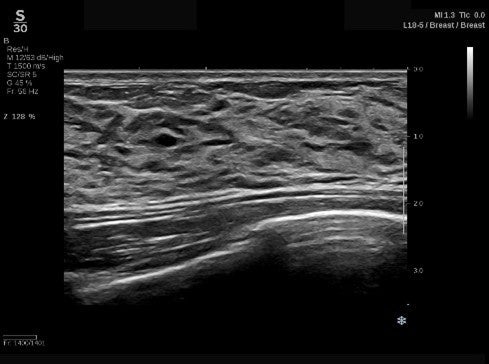

(1)独自のUltraFast™テクノロジーにより高画質な画像を実現

パワフルなプロセッサを搭載し、データを高速演算処理するUltraFast™ Imaging技術を駆使することにより、最大20,000フレーム/秒※1の処理速度で高速に画像を構築します。